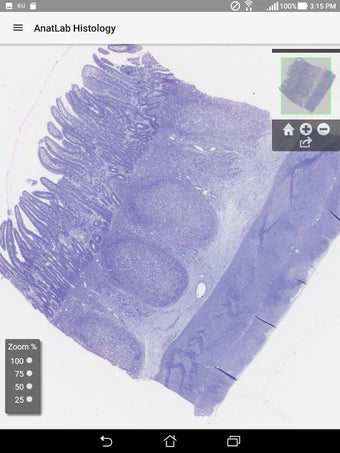

AnatLab Histology es una aplicación gratuita para Android desarrollada por Eolas Technologies Inc. que proporciona a los usuarios imágenes de diapositivas microscópicas de ultra alta resolución. Esta aplicación es una herramienta ideal para estudiantes, profesores, investigadores y el público en general. Con esta aplicación, pueden explorar el paisaje microscópico completo del cuerpo como si estuvieran mirando una colección de diapositivas reales en un microscopio físico. Tiene una función basada en la nube, la aplicación se puede acceder en cualquier dispositivo móvil Android, lo que la hace muy conveniente y accesible.

La aplicación ofrece una colección completa de imágenes de diapositivas microscópicas de histología que se pueden ver en ultra alta resolución. Las imágenes son de calidad excepcional y proporcionan una representación precisa del paisaje microscópico del cuerpo. La aplicación es fácil de usar y navegar, lo que permite a los usuarios explorar diferentes partes del cuerpo con facilidad.